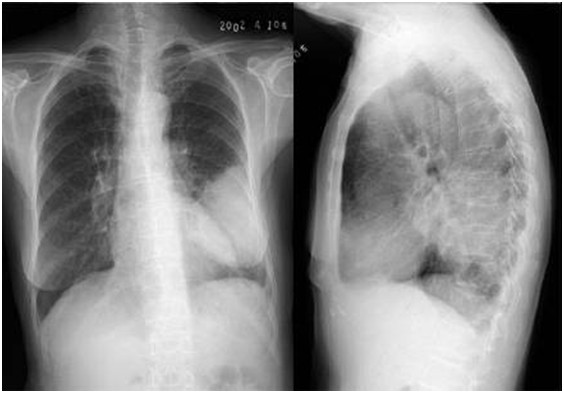

04卷-3.病史:男性,53歲,咳嗽、體重減輕4個(gè)月。診斷(本題滿分2.00分)

A.左下肺炎

B.左下包裹性積液

C.左下肺癌

D.左下肺結(jié)核

本題答案:C

題目解析:

【該題針對(duì)“ X線-肺癌 ”知識(shí)點(diǎn)進(jìn)行考核】